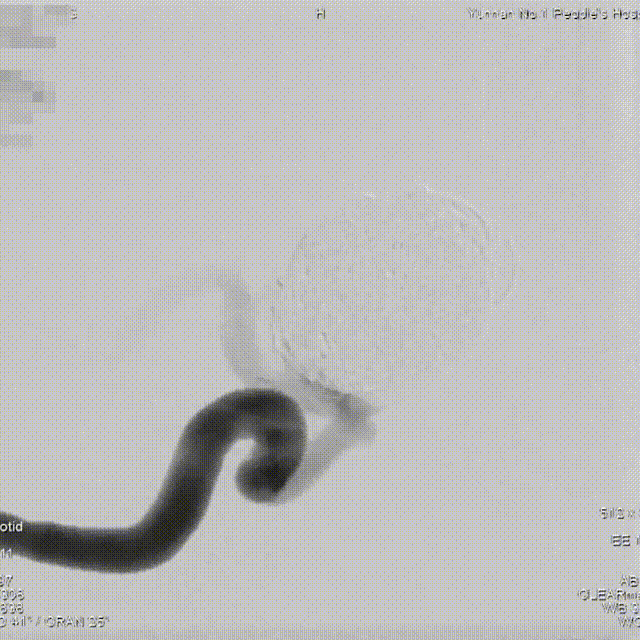

术前造影

术前造影提示:右侧颈内动脉眼动脉段大动脉瘤。

正位造影

侧位造影